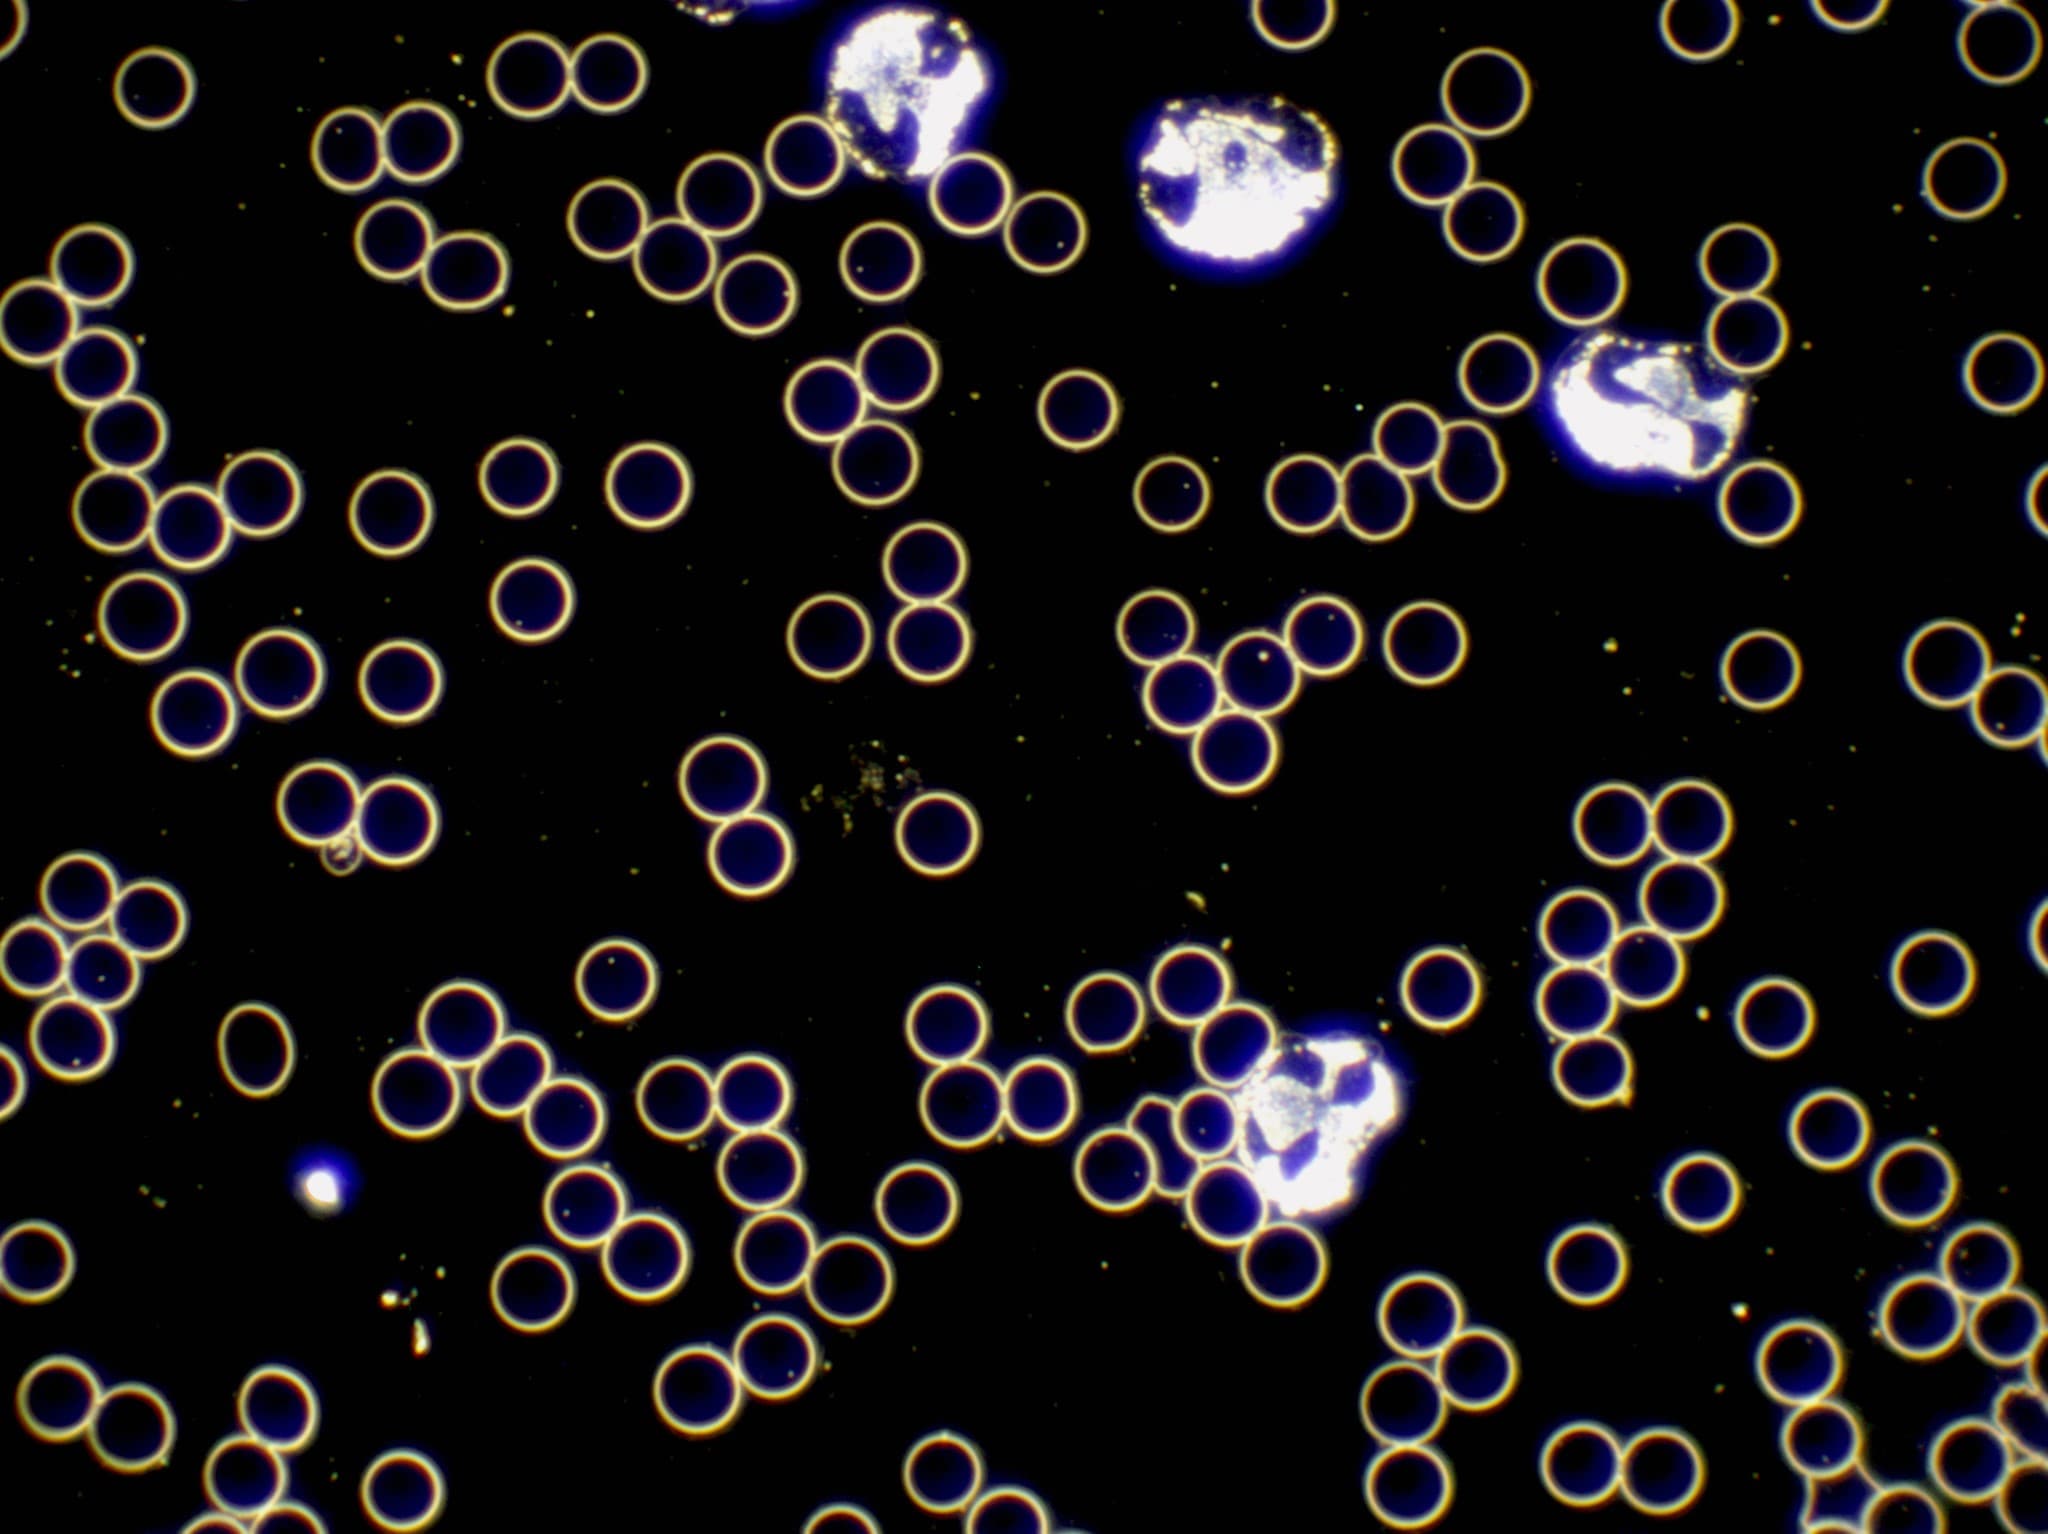

Laborwerte sagen Dir, wie viele Blutzellen Du hast. Die Dunkelfeldmikroskopie zeigt, wie lebendig sie sind. Bewegen sich Deine roten Blutkörperchen frei oder verklumpen sie? Arbeiten Deine weissen Blutkörperchen aktiv oder wirken sie träge? Diese Vitalität ist entscheidend für Deine Gesundheit und lässt sich nur im lebenden Blut erkennen.

Neben Zellen und Mikroben erscheinen manchmal kristalline Strukturen. Cholesterinkristalle glitzern wie kleine Diamanten und zeigen Fettstoffwechselstörungen. Harnsäurekristalle deuten auf Gicht Neigung, Nierenschwäche oder zu viel Fleischkonsum. Fibrin Fäden ziehen sich durchs Blut bei erhöhter Gerinnungsneigung. Jedes Detail erzählt eine Geschichte. Nichts im Blut ist Zufall. Alles hat Bedeutung. Und mit dieser Fülle an Informationen erstelle ich Deinen massgeschneiderten Therapieplan.